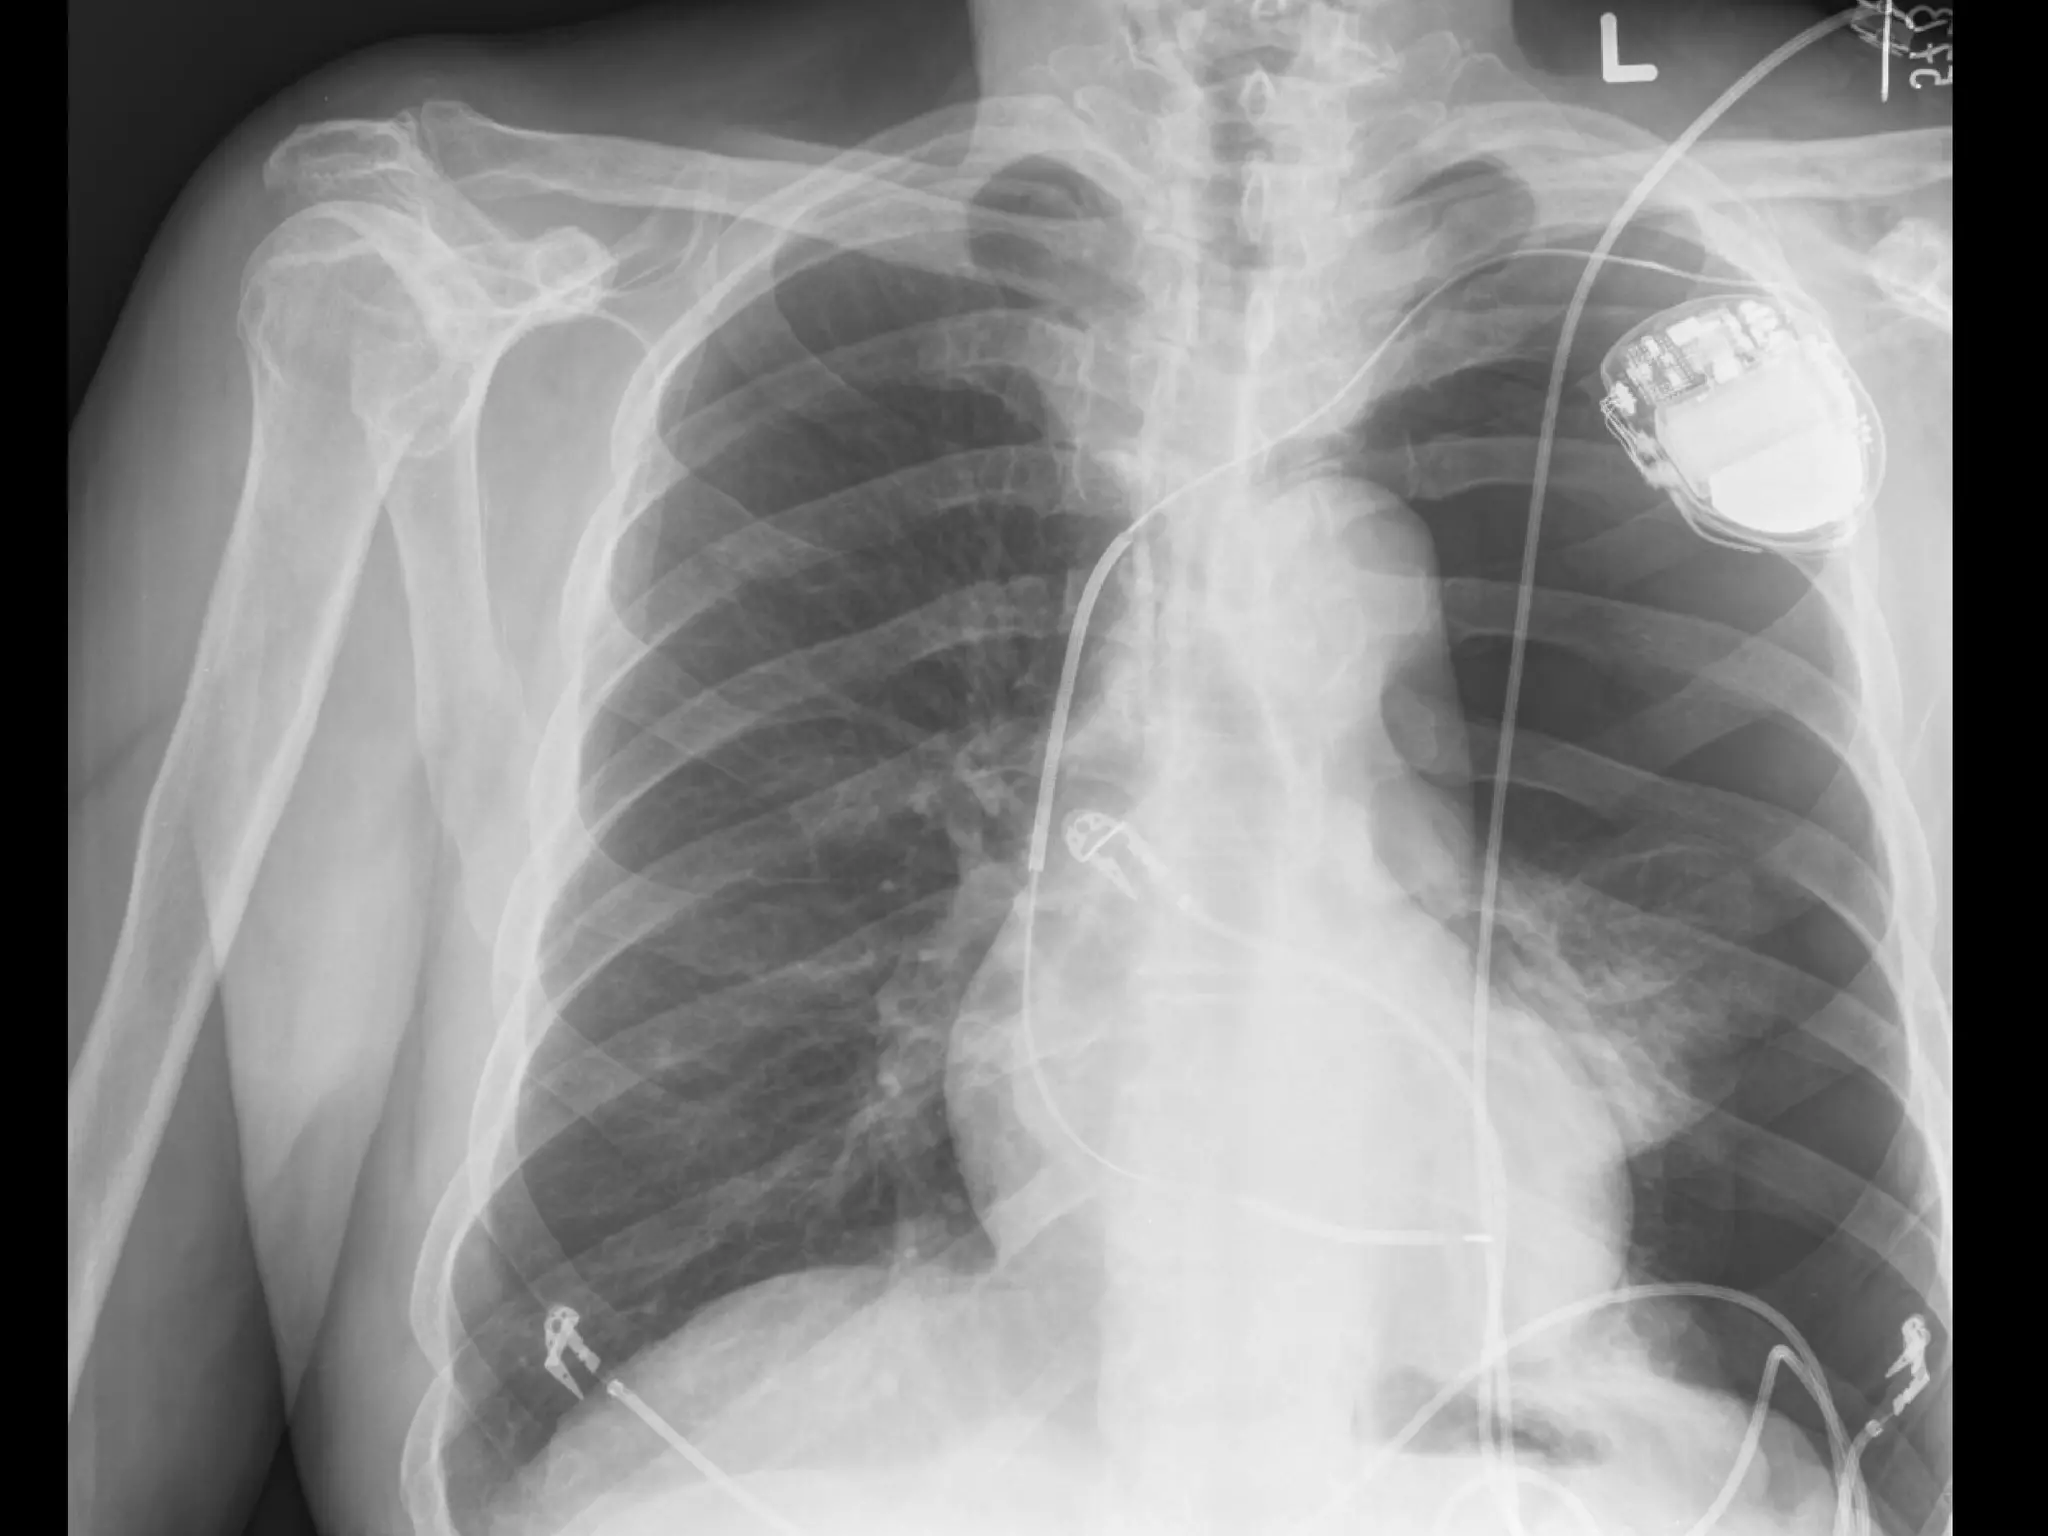

The Left Side is Sinister Left internal jugular has unique complications – thoracic duct injury Left inominate vein can be lacerated    hemothorax and    OR L IJ or SC catheter too proximal can lacerate SVC    death

The Left Sideis Sinister Left internal jugular has unique complications – thoracic duct injury Left inominate vein can be lacerated  hemothorax and  OR L IJ or SC catheter too proximal can lacerate SVC  death